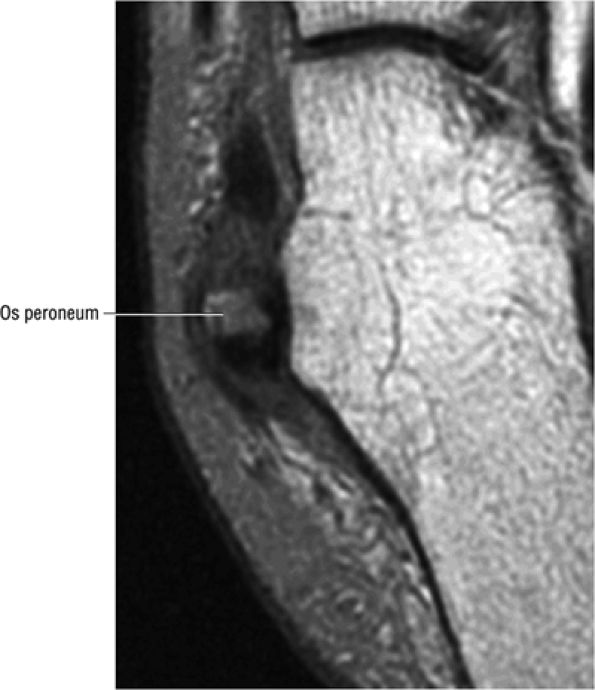

FIGURE 5.90 ● Normal marrow fat signal intensity associated with an asymptomatic os peroneum. The os peroneum is an accessory ossicle within the substance of the distal peroneus longus tendon near the cuboid.